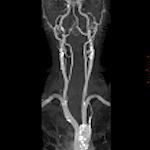

従来のシングルスライスCT、マルチスライスCTと比べ患者さんへの負担が少なく、診断能力の高い超高速ボリュームCT撮影装置。

②高速な撮影 : 全身を20秒、0.625mm厚にて撮影可能